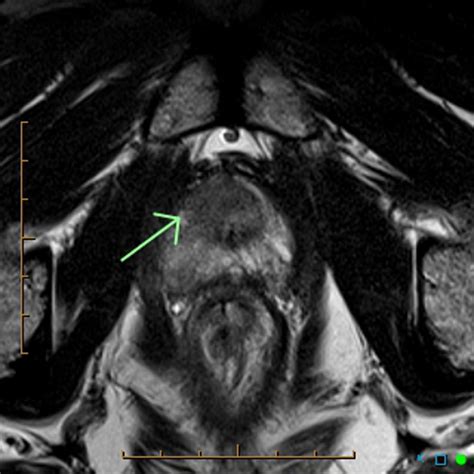

• T2-weighted imaging: Provides detailed anatomical images of the prostate.

• Diffusion-weighted imaging (DWI): Measures the movement of water molecules within tissues to detect areas of restricted diffusion, which may indicate cancer.